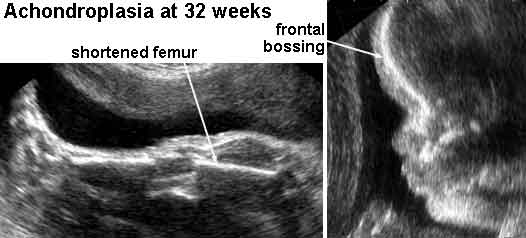

Dans la plupart des situations dans lesquelles les parents ont la stature normale, on peut seulement suspecter le diagnostic a bas� sur l'observation des membres d'une fa�on disproportionn�e courts dans le foetus par des ultrasons. Cependant, on observe des membres d'une fa�on disproportionn�e courts dans un groupe h�t�rog�ne de conditions. Dans la majorit� de ces caisses, le diagnostic sp�cifique ne peut pas �tre fait avec certitude except� par la radiographie en retard dans la grossesse ou plus habituellement apr�s naissance. Dans ces caisses, l'attention devrait �tre exerc�e en conseillant la famille. Dans ces cas peu fr�quents dans lesquels le diagnostic est sans �quivoque �tabli en raison de la nature familial du d�sordre ou par la radiographie pr�natale, le p�diatre peut discuter les issues suivantes comme appropri�es

8. Si la m�re est affect�e avec l'achondroplasia, une c�sarienne doit �tre ex�cut�e en raison d'un petit bassin. [ 9 ] Ce proc�d� chirurgical implique habituellement l'anesth�sie g�n�rale en raison de la st�nose spinale et du risque cons�quent de la m�re li�s � l'anesth�sie de la conduction (spinal/epidural). Une m�re affect�e avec l'achondroplasia peut d�velopper le compromis respiratoire dans le troisi�me trimestre de la grossesse, ainsi des �tudes pulmonaires de fonction de ligne de base devraient �tre faites. Une grossesse en danger pour le homozygosity devrait �tre suivie avec des mesures d'ultrasons � 14, 16, 18, 22, et 32 semaines de gestation afin de distinguer le homozygosity ou le heterozygosity des mod�les de croissance normaux dans le le foetus. Les �tudes diagnostiques de nouvelle ADN sont susceptibles de devenir disponibles.